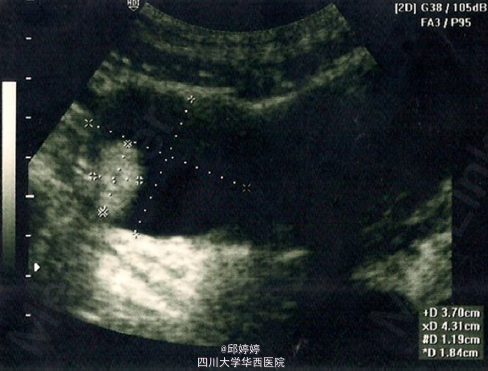

患者,女,20岁,右侧卵巢复发性成熟畸胎瘤伴CA-125增高,曾有两次手术史,第二次术后3年,出现双侧卵巢畸胎瘤。患者主要的临床表现为:间歇性腹痛,痛经,经期延长。第一次手术后一年,腹部超声检查发现(图1 示)患者右侧卵巢有一大小约4.3*3.7cm的高回声肿块,边界清晰,形态类似畸胎瘤,邻近子宫。第二次术后3年,患者再次出现腹痛,痛经等症状,增强CT检查发现(图2 示):左侧附件较大的异质性肿块,右侧附件高密度肿块。术后组织病理学检查确认为双侧附件成熟畸胎瘤,瘤体含脂质,角质,毛发等成分。 讨论:卵巢成熟畸胎瘤是一种良性肿瘤,且较为常见,但像本例这种双侧附件畸胎瘤且多次复发的病例是十分少见的。常规检查及术后超声随访监测对于这种复发性病例是十分必要的。 引自:Chang CF, Lin CK. BMC Womens Health. 2014 Apr 13;14:57